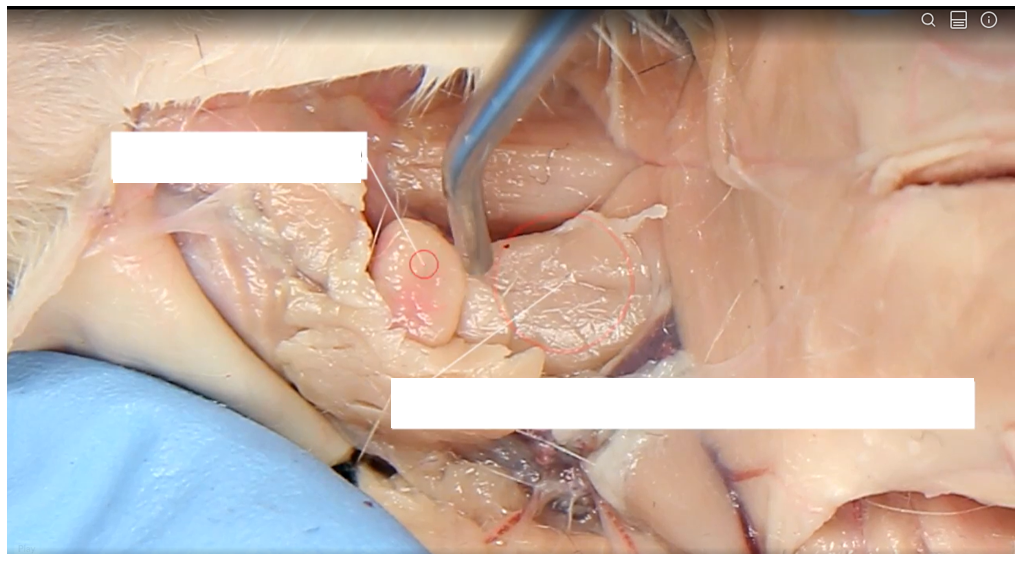

Submandibular salivary gland

Lymph node

Parotid salivary gland